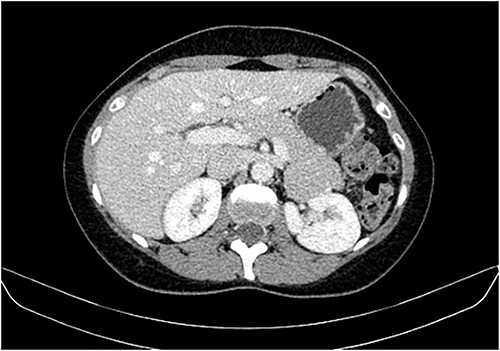

During a screening imaging examination of her liver disease, a lesion suspected of malignancy was detected. The ultrasound disclosed a hypoechoic nodule, vaguely heterogeneous, located in segment VII, subcapsular, and with ~22 mm in diameter (Fig. 1). Liver blood tests and serum alpha-fetoprotein level were normal. For better characterization, a CT scan was performed. The CT showed, in addition to signs of chronic liver disease, the presence of a solid subcapsular nodule of segment VII, measuring 23 mm, with hypervascular behavior in the arterial phase (Fig. 2) and washout in late venous phase (Fig. 3).

CT scan showing, in addition to signs of chronic liver disease, the presence of a solid subcapsular nodule of segment VII, measuring 23 mm, with hypervascular behavior in the arterial phase.